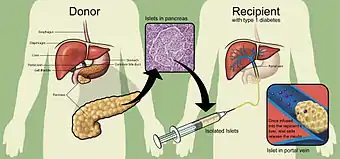

Islet transplantation is the transplantation of isolated islets from a donor pancreas into another person. It is a treatment for type 1 diabetes.[1] Once transplanted, the islets begin to produce insulin, actively regulating the level of glucose in the blood.

Islets are usually infused into the person's liver.[2] If the cells are not from a genetically identical donor the person's body will recognize them as foreign and the immune system will begin to attack them as with any transplant rejection. To prevent this immunosuppressant drugs are used. A study from 2005 showed that islet transplantation has progressed to the point that 58% of the people were insulin independent one year after the operation.[3] A review published 2016 reported a 50 – 70% rate of insulin independence after five years, in five studies from leading transplant centers published 2005 – 2012.[4]

The goal of islet transplantation is to infuse enough islets to control the blood glucose level removing the need for insulin injections. For an average-size person (70 kg), a typical transplant requires about one million islets, isolated from two donor pancreases. Because good control of blood glucose can slow or prevent the progression of complications associated with diabetes, such as nerve or eye damage, a successful transplant may reduce the risk of these complications. But a transplant recipient will need to take immunosuppressive drugs that stop the immune system from rejecting the transplanted islets.

Researchers use a mixture of highly purified enzymes (Collagenase) to isolate islets from the pancreas of a deceased donor. Collagenase solution is injected into the pancreatic duct which runs through the head, body and tail of the pancreas. Delivered this way, the enzyme solution causes distension of the pancreas, which is subsequently cut into small chunks and transferred into so-called Ricordi's chamber, where digestion takes place until the islets are liberated and removed from the solution. Isolated islets are then separated from the exocrine tissue and debris in a process called purification.

During the transplant, a radiologist uses ultrasound and radiography to guide placement of a catheter through the upper abdomen and into the portal vein of the liver. The islets are then infused through the catheter into the liver. The person will receive a local anesthetic. If a person cannot tolerate local anesthesia, the surgeon may use general anesthesia and do the transplant through a small incision. Possible risks of the procedure include bleeding or blood clots.